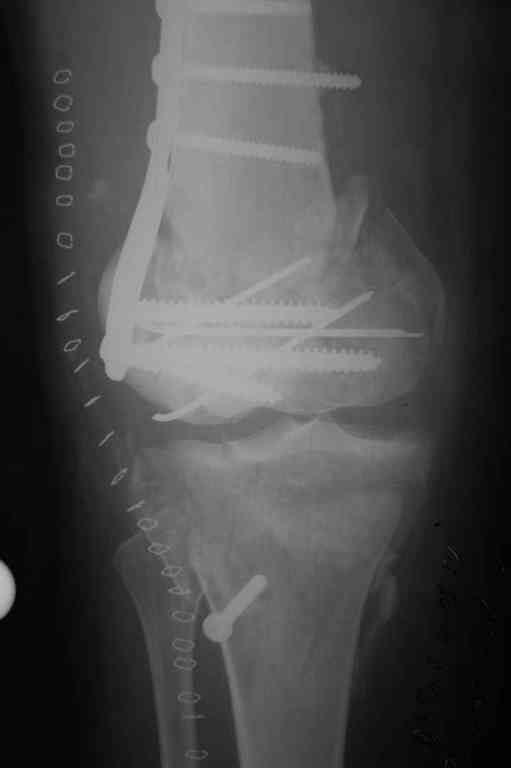

Здесь применение материала Plexur http://www.plexur.com для пластики при дефектах кости у больной с огнестрельной раной латерального тибиал плато с повреждением малоберцового нерва. Несмотря на интактный медиальный мышелок, для профилактики от вальгуса установлен АВФ и сделана ангиограмма.

После нескольких обработок и вакуумирования, поэтапно сделана фиксация тибиального бугра шурупами. И окончательную фиксацию закончили латеральной пластиной для тибиал плато и установкой пластического материала.

Для закрытия мягкотканых дефектов привлечена другая служба.